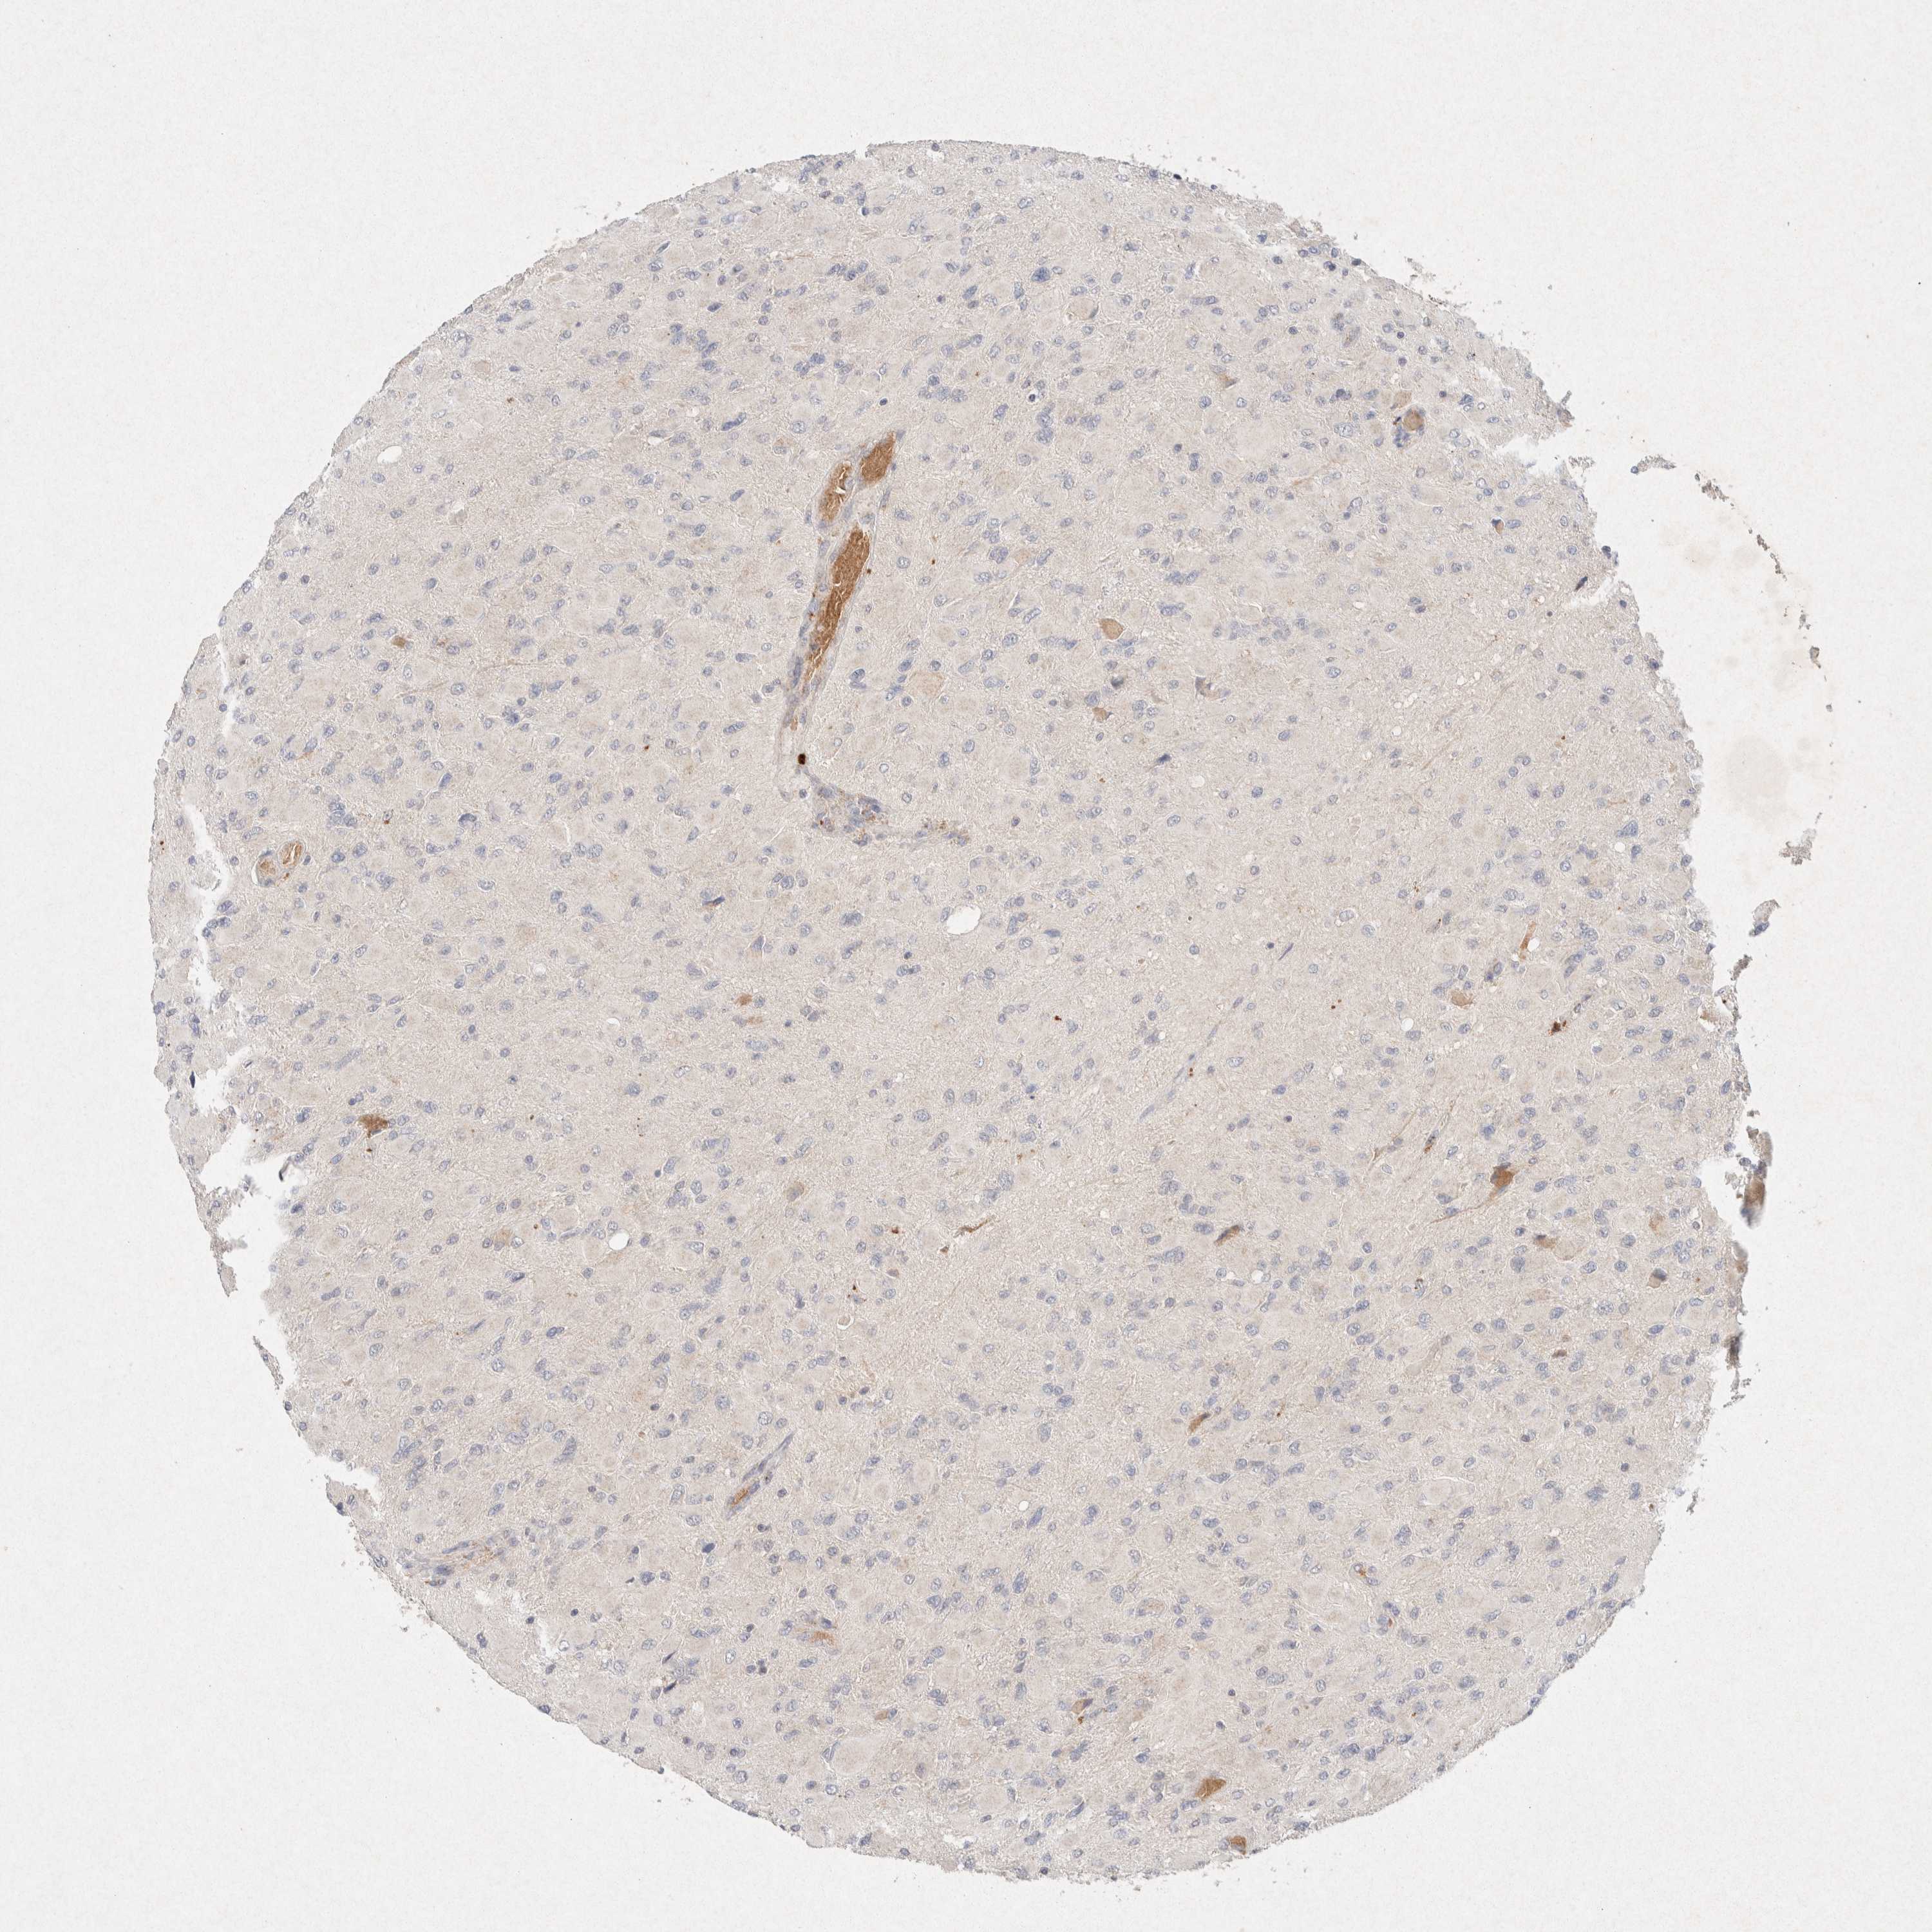

GLIOMA - Protein expressioni

A mouse-over function shows sample information and annotation data. Click on an image to view it in a full screen mode. Samples can be filtered based on level of antibody staining by selecting one or several of the following categories: high, medium, low and not detected. The assay and annotation is described here.

Note that samples used for immunohistochemistry by the Human Protein Atlas do not correspond to samples in the TCGA dataset.

Antibody stainingi

Antibody staining in the annotated cell types in the current human tissue is reported as not detected, low, medium, or high, based on conventional immunohistochemistry profiling in selected tissues. This score is based on the combination of the staining intensity and fraction of stained cells.

Each image is clickable and will lead to virtual microscopy that enables deeper exploration of all samples and also displays staining intensity scores, fraction scores and subcellular localization as well as patient and tissue information for each sample.

Antibody HPA042141

Antibody CAB022449

Staining

High

Medium

Low

Not detected

Intensity

Strong

Moderate

Weak

Negative

Quantity

>75%

75%-25%

<25%

None

Location

Nuclear

Cytoplasmic/membranous

Cytoplasmic/membranous,nuclear

Glioma, malignant, High grade

Glioma, malignant, Low grade